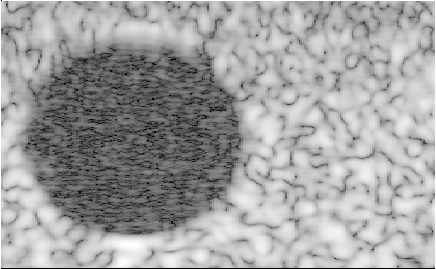

Alpinion_L3-8_CPWC_hypoechoic.uff

Alpinion CPWC hypoechoic phantom